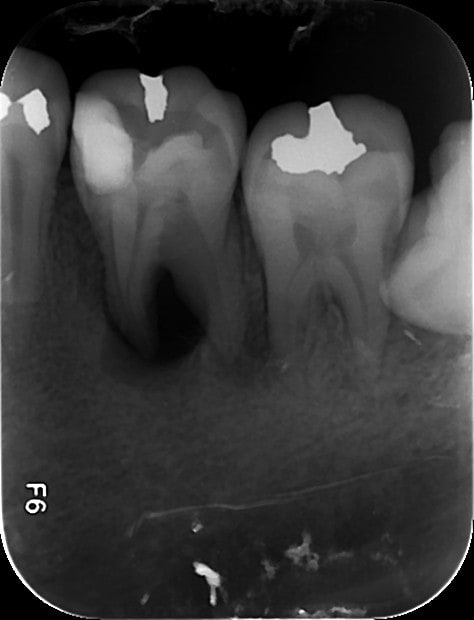

1   02022015 xhyug0 - Eugenol

3   02022015 athoja - Eugenol

2   02022015 jomvv1 - Eugenol

4   06022015 zewfwa - Eugenol

5   06022015 uym87j - Eugenol